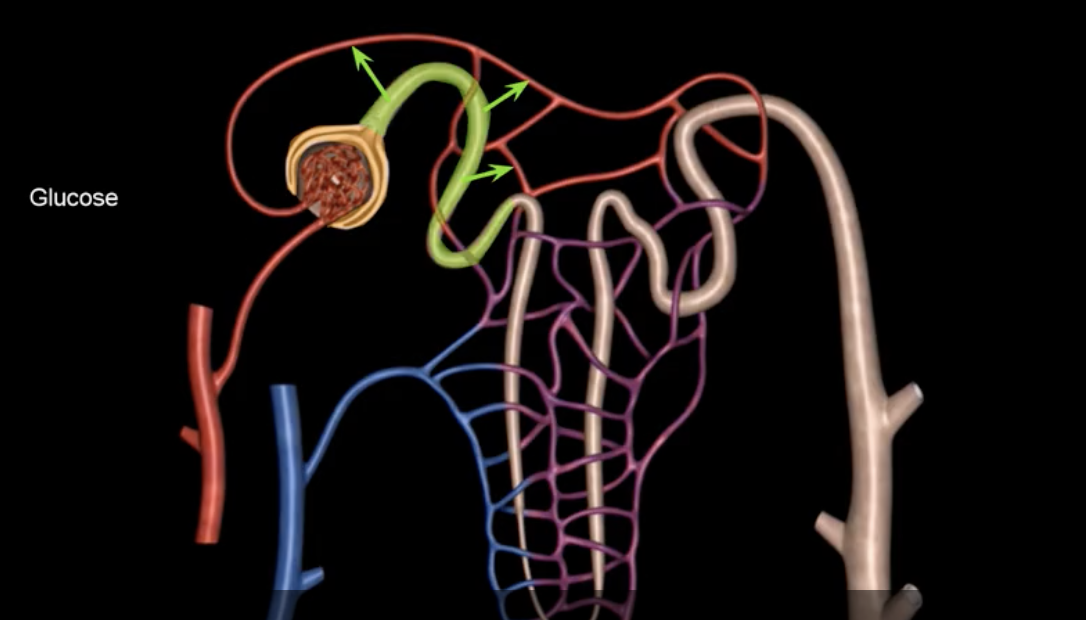

afferent arteriole

yellow

glomerulus

green

efferent arteriole

purple

orange: peritubular capillaries

green: vasa recta

efferent arteriole give rise to orange and green